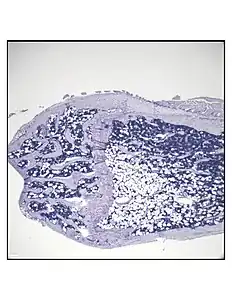

This figure demonstrates the use of MRI imaging (9.4T scanner) along with advanced image processing to quantify BMAT. The images and graph demonstrate that BMAT is higher in obese compared with lean mice. B6 mice were fed HFD from age 4 wk until age 16 wk. BMAT was quantified by MRI. A) n=10 superimposed group average images are shown B) BMAT normalized to bone volume in each group._.jpg.webp) Representative distal femur histologic section of a 16-week-old healthy C57BL/6 mouse demonstrating a typical quantity of marrow adipocytes.

Representative distal femur histologic section of a 16-week-old healthy C57BL/6 mouse demonstrating a typical quantity of marrow adipocytes. Representative distal femur histologic section of a 16-week-old C57BL/6 mouse after 6 weeks of calorie restriction demonstrating an increased quantity of marrow adipocytes.

Representative distal femur histologic section of a 16-week-old C57BL/6 mouse after 6 weeks of calorie restriction demonstrating an increased quantity of marrow adipocytes.